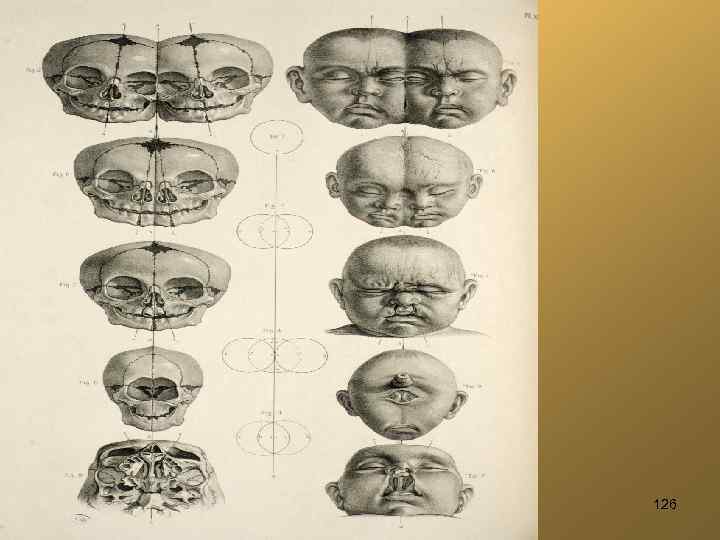

126

127 рис. Walter, Johann Gottlieb, 1775

Циклопизм, "жаберные щели" 128